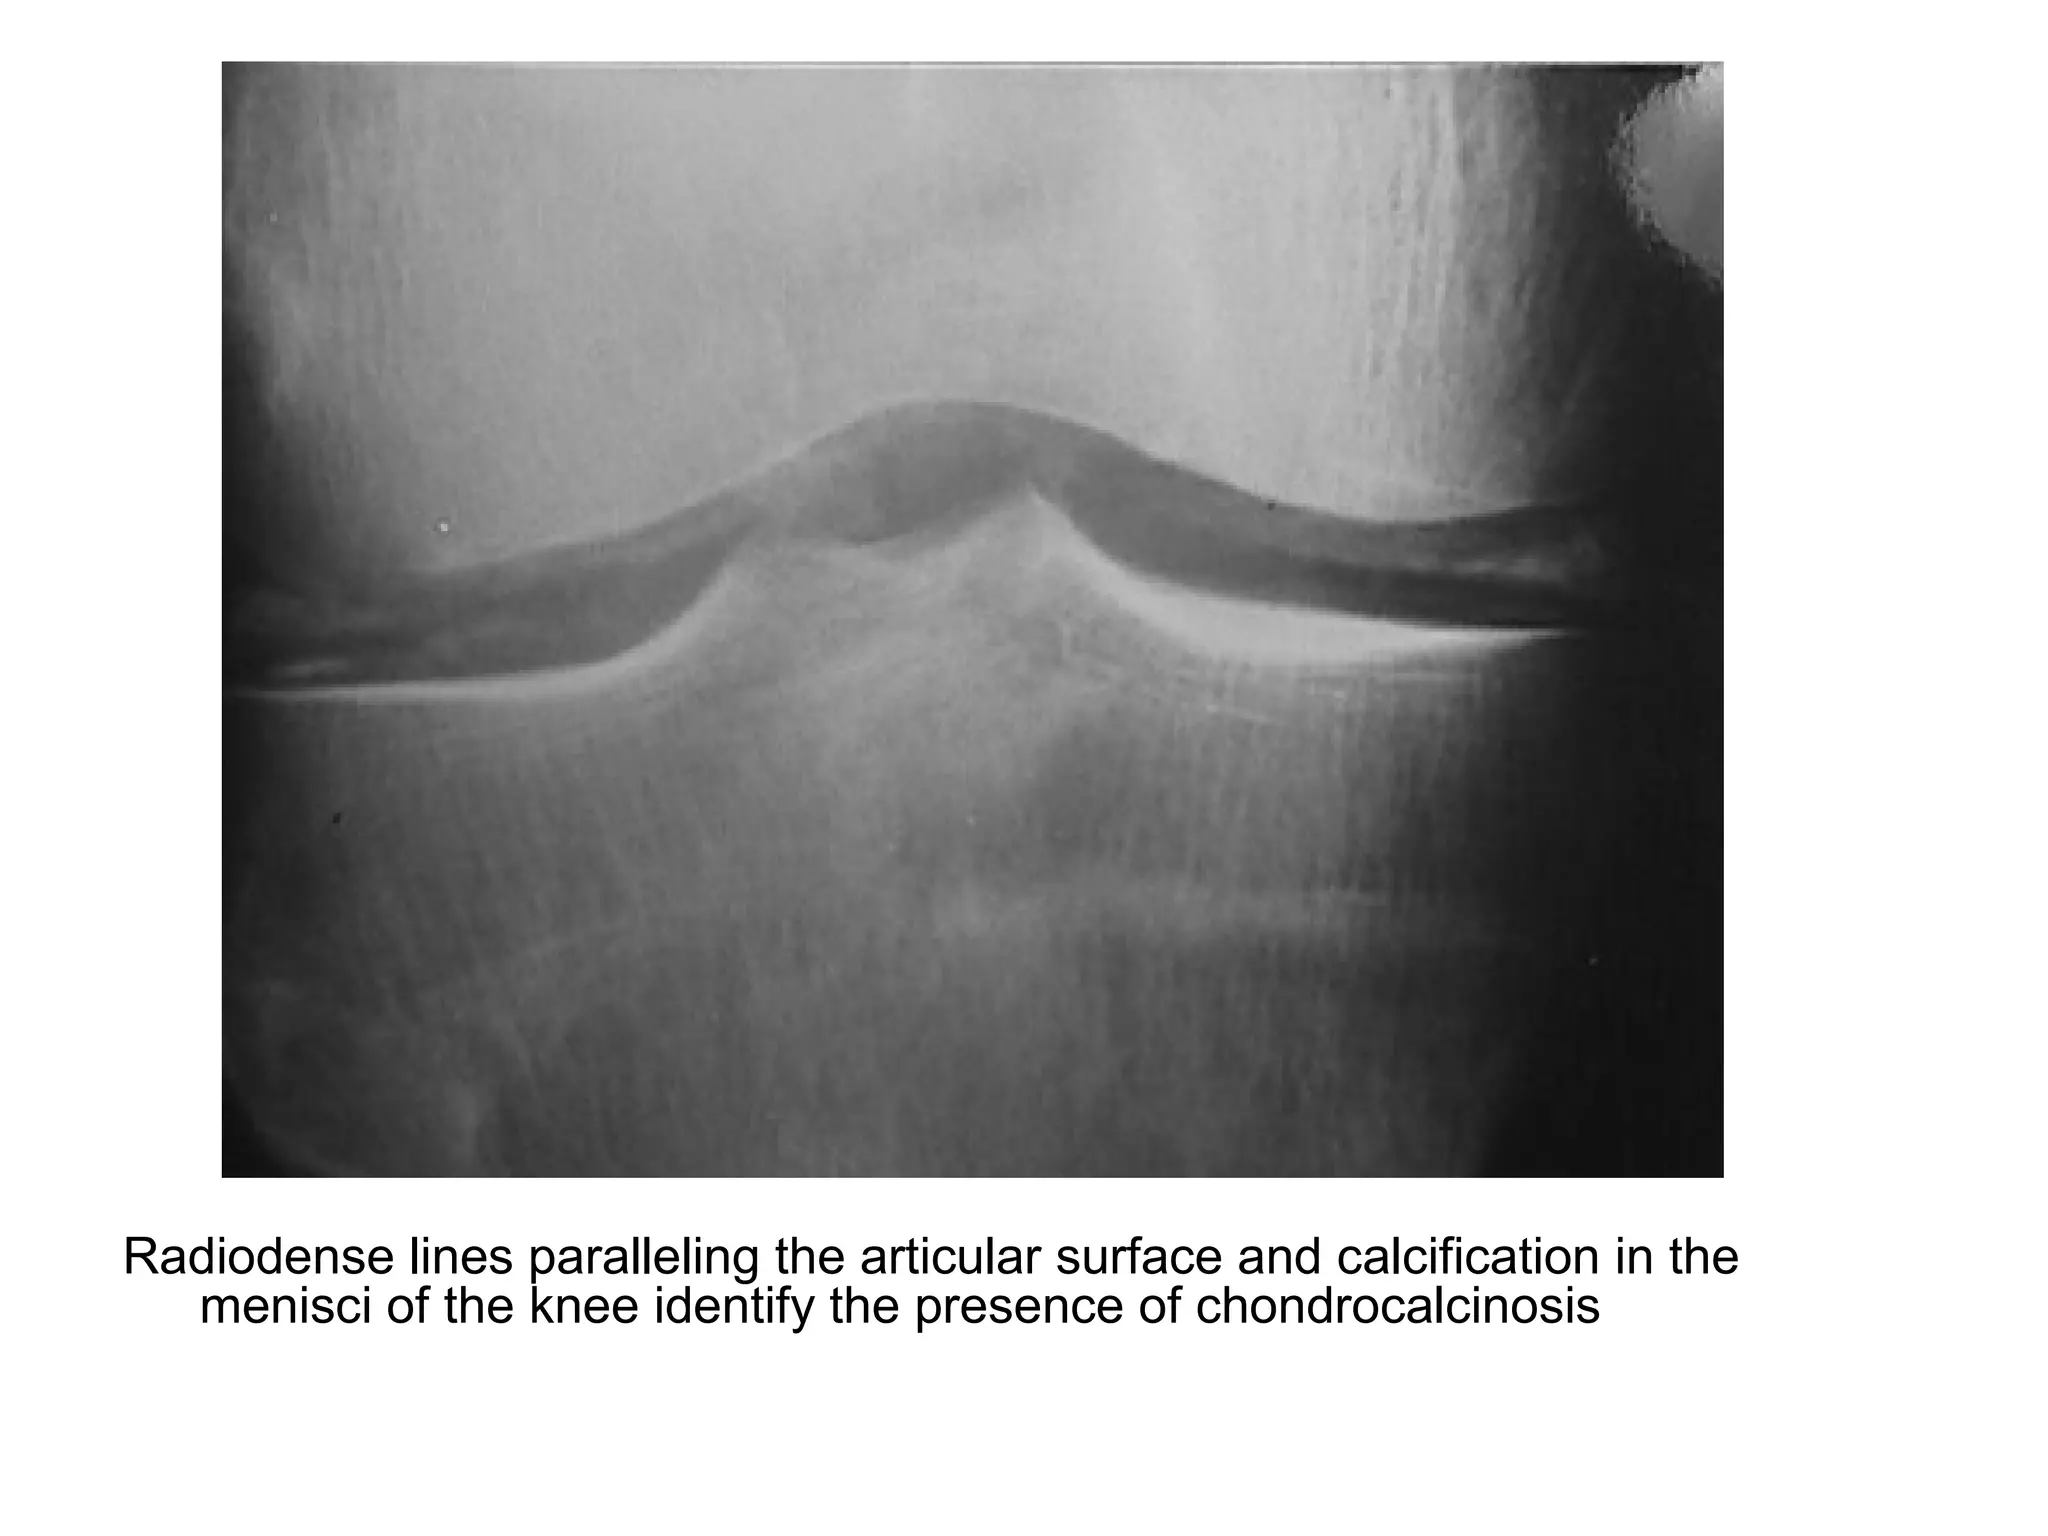

Radiodense lines paralleling the articular surface and calcification in the

menisci of the knee identify the presence of chondrocalcinosis

Chondrocalcinosis within the meniscal cartilage of the knee